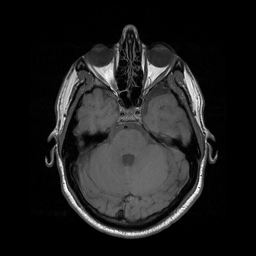

Motion artifacts are a primary source of magnetic resonance (MR) image quality deterioration with strong repercussions on diagnostic performance. Currently, MR motion correction is carried out either prospectively, with the help of motion tracking systems, or retrospectively by mainly utilizing computationally expensive iterative algorithms. In this paper, we utilize a novel adversarial framework, titled MedGAN, for the joint retrospective correction of rigid and non-rigid motion artifacts in different body regions and without the need for a reference image. MedGAN utilizes a unique combination of non-adversarial losses and a novel generator architecture to capture the textures and fine-detailed structures of the desired artifacts-free MR images. Quantitative and qualitative comparisons with other adversarial techniques have illustrated the proposed model's superior performance.

翻译:移动文物是磁共振(MR)图像质量恶化的一个主要来源,对诊断性能产生强烈影响。目前,MR运动的校正要么是预期性的,借助运动跟踪系统,要么是追溯性的,主要是利用成本昂贵的计算迭代算法。在本文中,我们使用名为MedGAN的新颖的对抗性框架,联合追溯性地校正不同身体区域的硬性和非硬性运动文物,而不需要参考图像。 MedGAN利用非对抗性损失和新型生成器结构的独特组合来捕捉无MR图象的纹理和精细详细结构。 与其他对抗性技术的定量和定性比较展示了拟议模型的优异性表现。